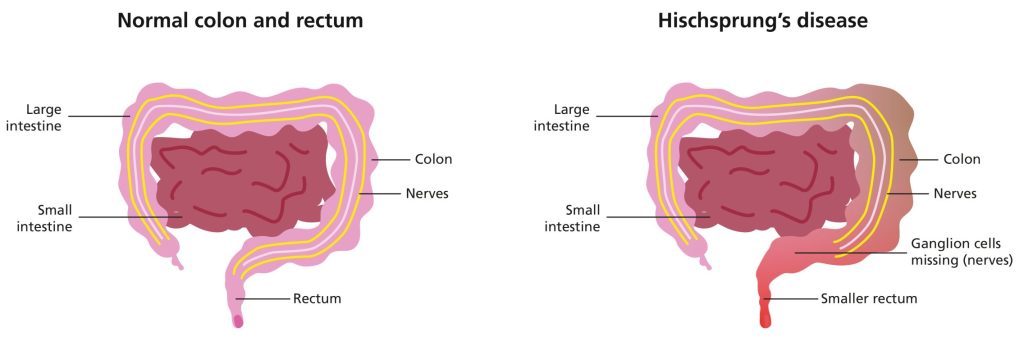

بیماری هیرشپرونگ (HSCR یا Hirschsprung Disease) یک نقص مادرزادی است. این اختلال با عدم وجود سلولهای عصبی خاص (گانگلیونها یا ganglions) در قسمتی از روده در نوزاد مشخص میشود. فقدان سلولهای گانگلیونی باعث میشود که عضلات روده توانایی خود را برای حرکت مدفوع از طریق روده (پریستالسیس یا peristalsis) از دست بدهند. پریستالسیس یک فرآیند طبیعی بدن است.

پریستالسیس انقباضات موج مانندی را از عضلات پوشاننده روده ایجاد میکند. این انقباضات، مدفوع و سایر مواد زائد را از طریق دستگاه گوارش به حرکت در میآورد. پریستالسیس بی اثر منجر به برگشت مدفوع در روده میشود. افراد مبتلا ممکن است دچار یبوست و انسداد جزئی یا کامل روده شوند.

علائم و نشانههای HSCR به دلیل عدم رشد سلولهای عصبی خاص به نام گانگلیون (ganglions) در قسمتی از روده بزرگ نوزاد رخ میدهد. HSCR گاهی اوقات نوروکریستوپاتی (neurocristopathy) نامیده میشود، به این معنی که این اختلال ناشی از ناهنجاری در سلولها و بافتهایی است که از تاج عصبی (neural crest) ایجاد میشود.

تاج عصبی (neural crest) گروهی از سلولهای موقتی است که در جنین در حال رشد یافت میشود. تاج عصبی به انواع مختلفی از سلولهای بدن تبدیل میشود. در HSCR، گانگلیونها به درستی از تاج عصبی رشد نمیکنند. از آن جایی که گانگلیونها در روده وجود ندارند، مدفوع نمیتواند از طریق روده و از طریق پریستالیس به خارج از بدن منتقل شود.

طول روده ای که در HSCR تحت تاثیر قرار میگیرد میتواند متفاوت باشد. تقریباً در 80 درصد از نوزادان مبتلا، این روده بزرگ است که معمولاً کولون و رکتوم نامیده میشود که تحت تأثیر قرار میگیرند. رکتوم (rectum) آخرین قسمت روده بزرگ است و مقعد را به کولون سیگموئید (sigmoid colon) متصل میکند. گفته میشود نوزادانی که سلولهای گانگلیونی در رکتوم و کولون سیگموئید ندارند، به بیماری هیرشپرونگ «بخش کوتاه یا short-segment» مبتلا هستند.